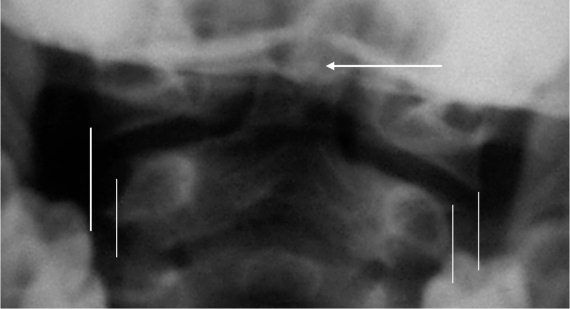

Псевдоперелом Джефферсона (рис. 4. 7)

Определяется на трансоральных рентгенограммах как выстояние суставных площадок атланта (до 6 мм) над суставными площадками аксиса. Типичный рентгенологический феномен у детей до 4 лет, но встречается и до 7-летнего возраста [9]. Связан с отсутствием окостенения латеральных поверхностей суставных фасеток CII.

Ядро окостенения верхушки зубовидного отростка (рис. 4. 7)

Визуализируется отдельно от тела у 26 % детей от 6 до 8 лет, что может имитировать перелом [2, 3].

Рис. 4.7. Трансоральная рентгенограмма здорового ребенка 4 лет. Вертикальными линиями ограничены видимые края суставных площадок CI и CII. Стрелкой указано отдельное ядро окостенения верхушки зубовидного отростка, расположенное в седловидной выемке основной части эпистрофея